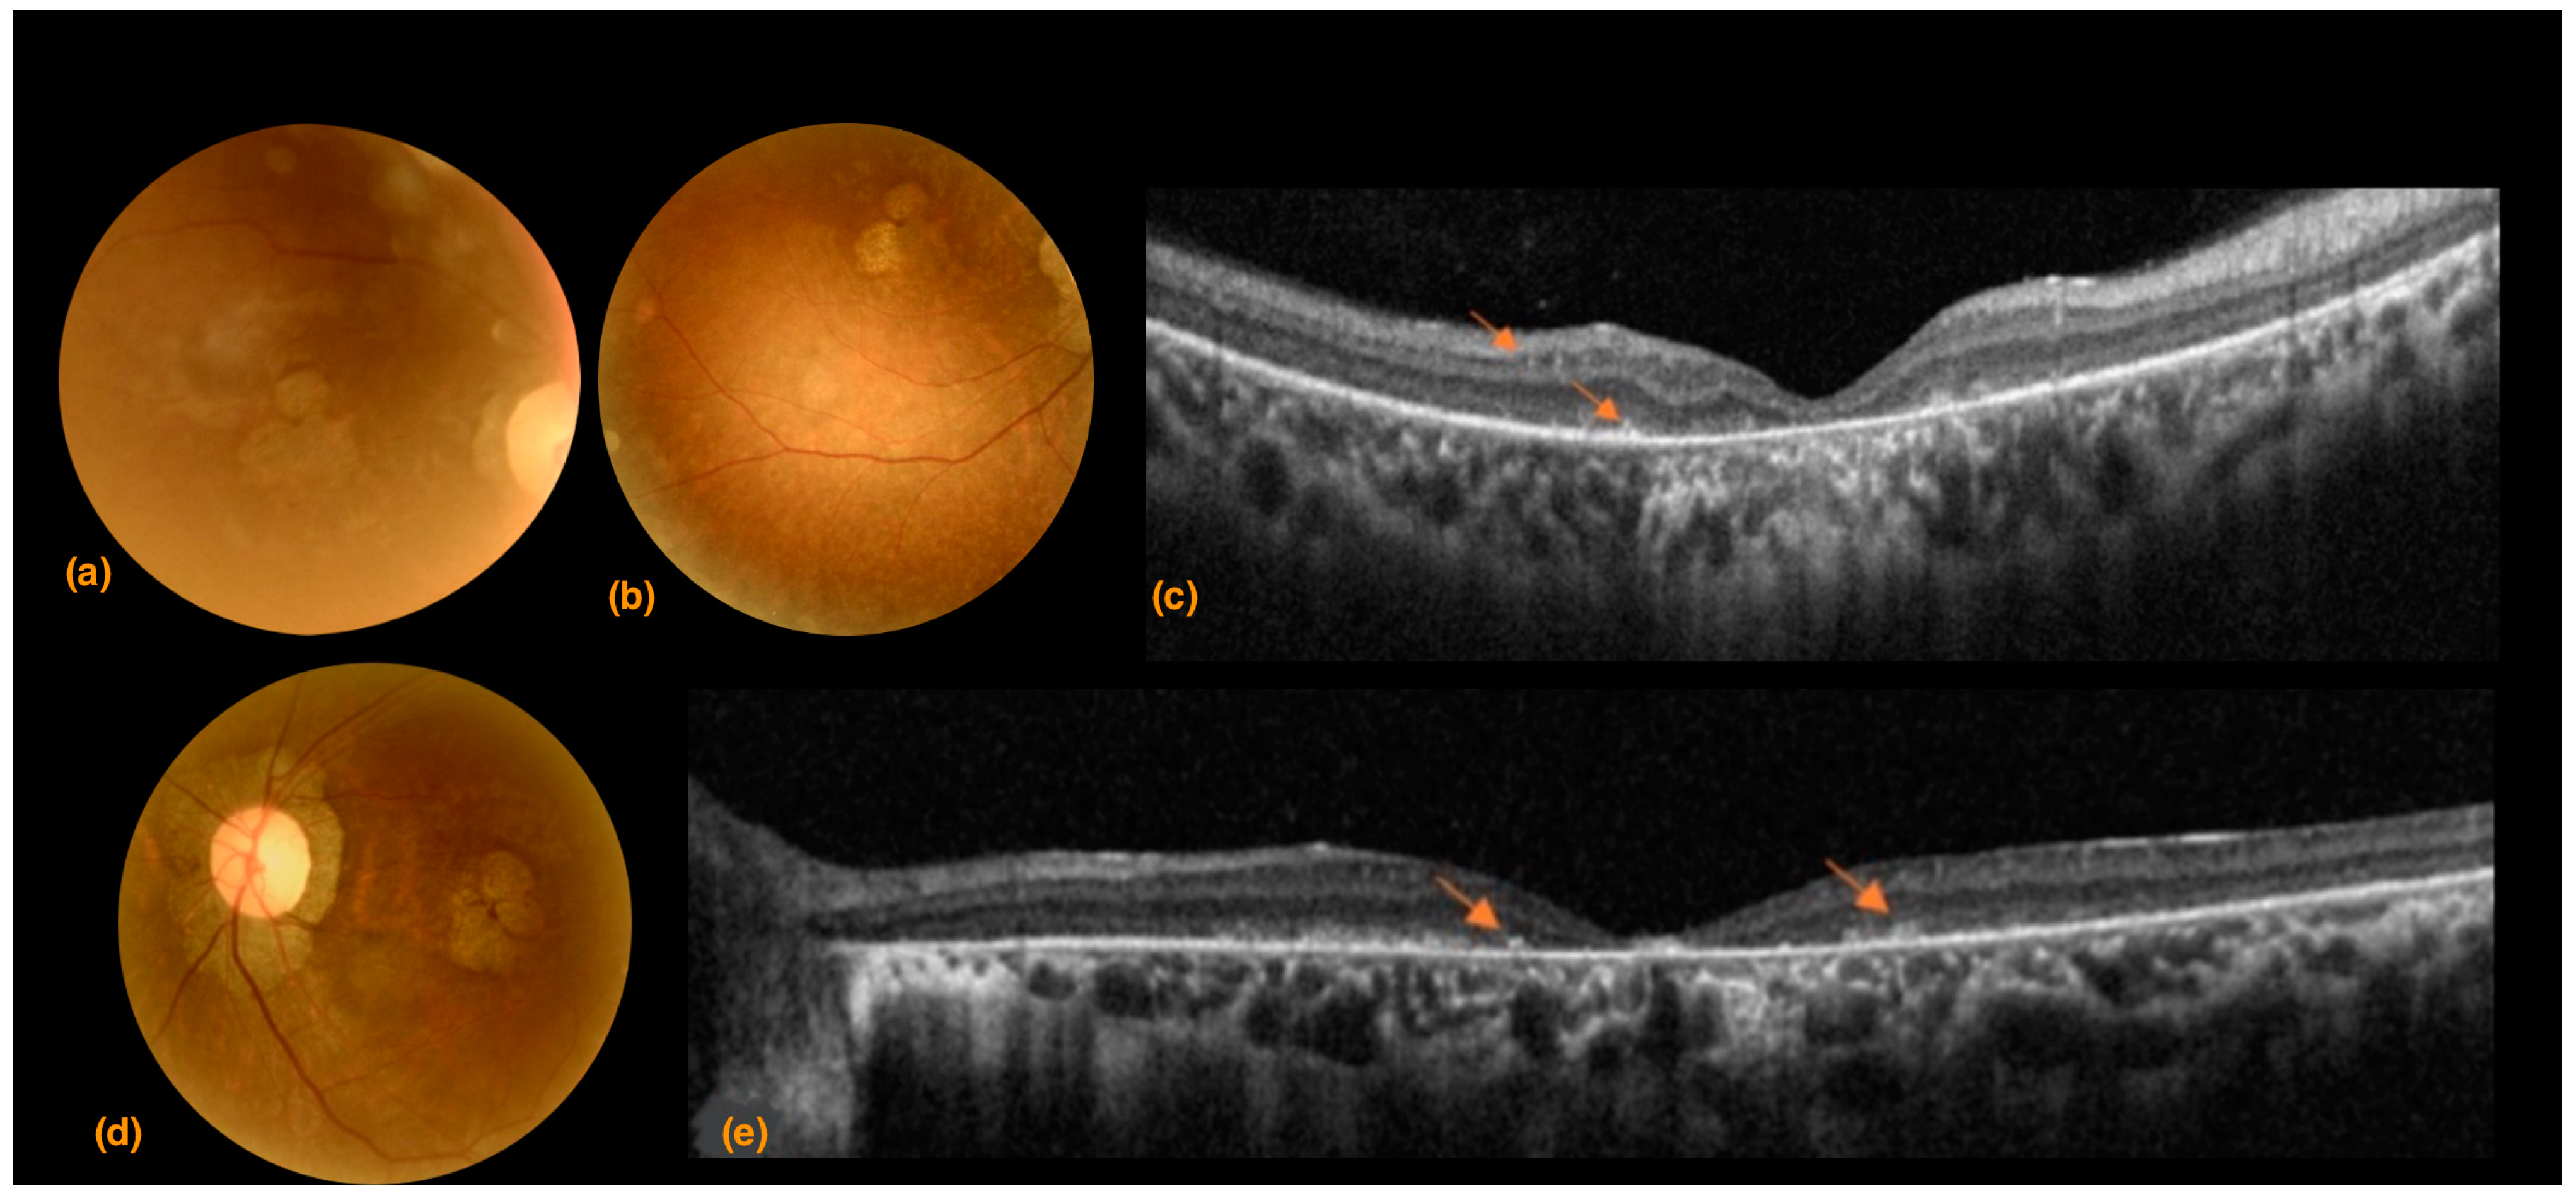

3.2. Case 2